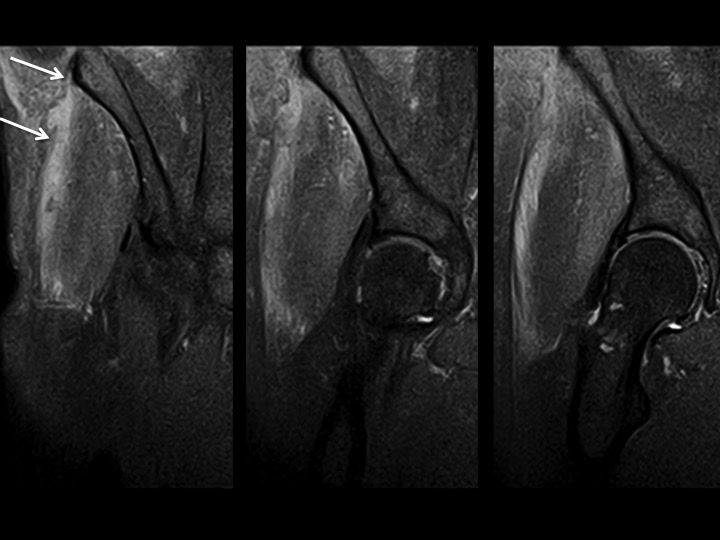

69M 1 week hip pain

There is complete retracted avulsion of proximal iliotibial band at its iliac tubercle origin, with contiguous delaminating tear of the gluteus medius fascia, subfascial hemorrhage and low grade G medius muscle strain. I have only ever seen proximal ITB tears in women, with few non-insertional tears and gluteal fascial tears more common (in my experience) in men. This man has a history of diabetes. I dont know if he had trauma.

iliotibial band ( RID2855 )